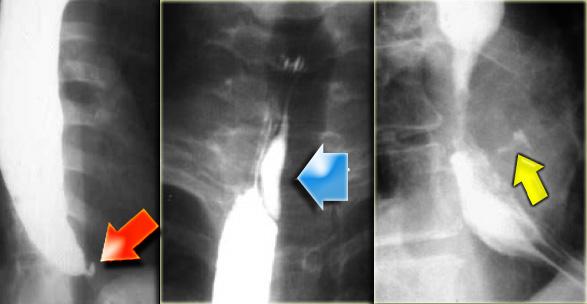

Bên trái là hình ảnh một bệnh nhân có biến chứng sau nội soi phức tạp.

Can thiệp dụng cụ gây rách niêm mạc và tụ máu trong thành thực quản dạng bóc tách, tạo ra hình ảnh lòng đôi với dải niêm mạc phân tách (các mũi tên).

Ngoài cùng bên trái là hình ảnh thoát thuốc cản quang trong thành thực quản (mũi tên) sau nong đoạn xa điều trị co thắt tâm vị.

Ở giữa là hình ảnh thoát thuốc cản quang trong thành thực quản (mũi tên) sau nội soi phức tạp.

Bên phải là hình ảnh thủng thực quản sau sinh thiết với thuốc cản quang thoát ra ngoài lòng thực quản (mũi tên).